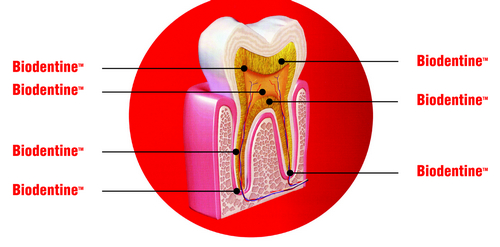

Биодентин – один материал для решения 7 проблем.

- Пломбирование полостей.

- Прямое покрытие пульпы.

- Пломбирование после пульпотомии.

- Апексификация.

- Устранение корневых и фуркационных перфораций.

- Устранение внутренних и наружных резорбций корня.

- Ретроградное пломбирование и закрытие верхушки корня после резекции

Превосходные герметизирующие свойства обеспечены великолепной влагоустойчивостью в сочетании с отсутствием усадки, благодаря отсутствию полимеров в составе.